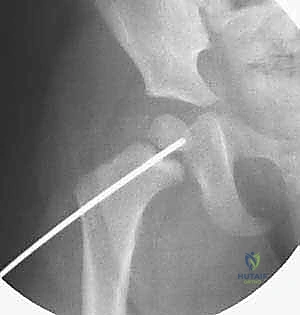

2. الرد المغلق أو المفتوح (Reduction)

- الرد المغلق: تحت التخدير العام، وبمساعدة جهاز الأشعة المرئية (C-arm)، يقوم الدكتور هطيف بتحريك الساق بلطف وبطريقة هندسية دقيقة لإعادة العظام المكسورة إلى مكانها دون فتح جراحي كبير. يتم تفريغ التجمع الدموي داخل المفصل (Capsulotomy) لتخفيف الضغط عن الأوعية الدموية.